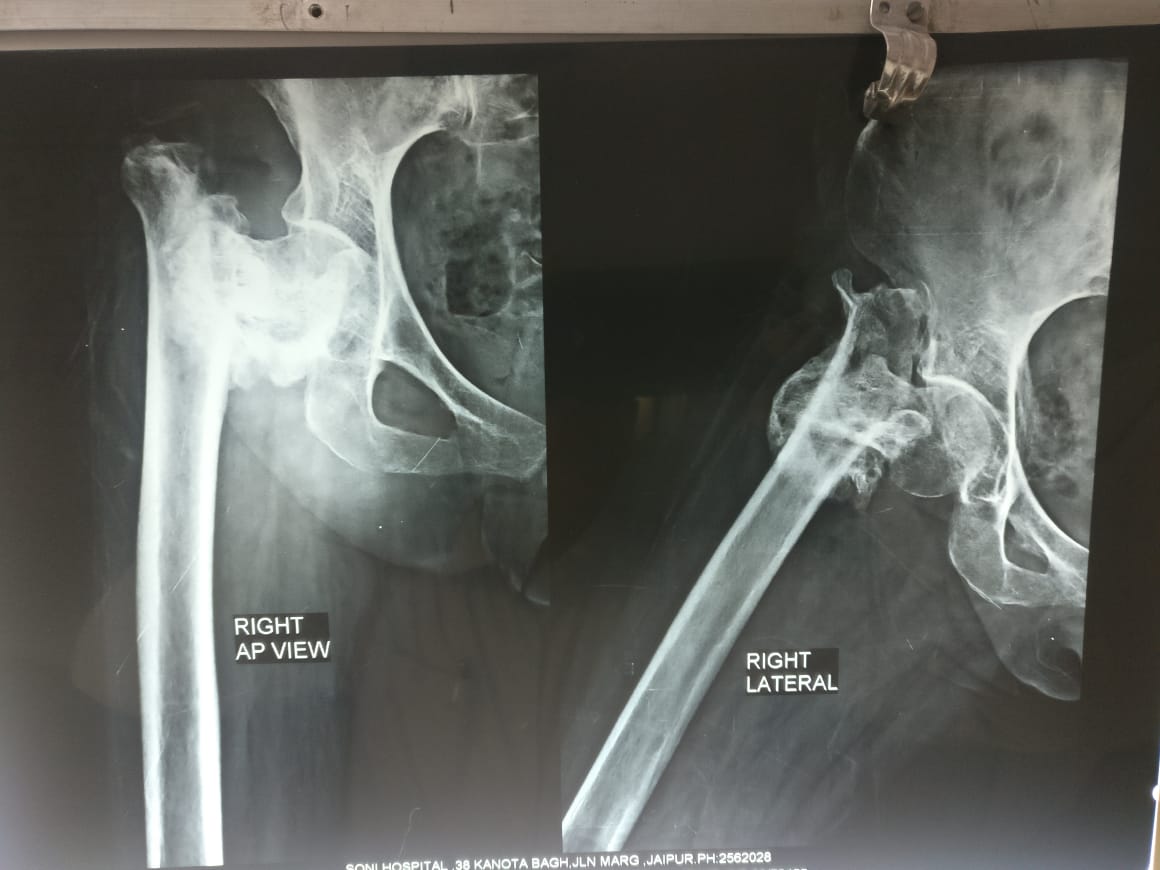

Hip fracture